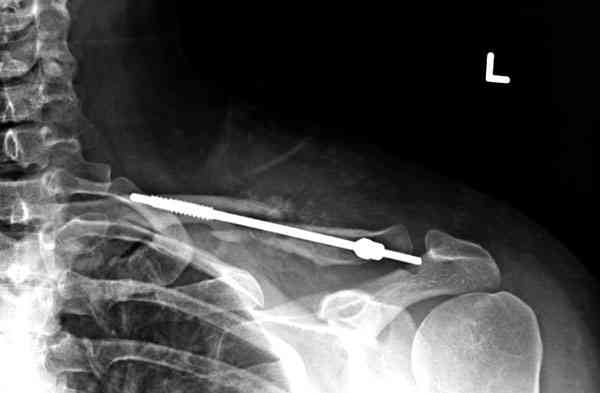

Недавно разбирали случай ложного сустава.

45 летная женщина после автоаварии, алкоголь 163 и 20 летним стажем курения.

Консервативное лечение, через 8 мес. операция Rockwood pin с костной пластикой в нашем городе другим врачом. После 8 недели падение, гвоздь удален оперирующим хирургом, больная направлена к нам. Фиксация реконструктивной пластиной с трикортикальным графтом, добавлен BMP-2. Для стабилизации фиксацию провели через акромион.

Вот уже два месяца больная также продолжает жаловаться на боли, буквально на днях удалили акромиальную часть пластины с специальной пилой с алмазным покрытием для медицинского металла. До сих пор судьба ложного сустава неизвестна....